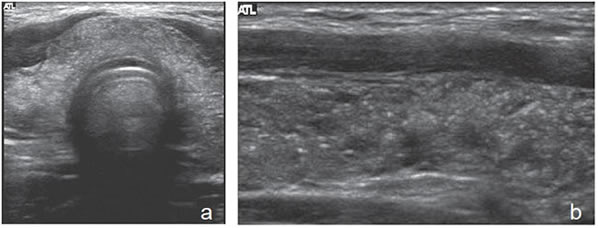

3. Ecogenicidad

El parénquima tiroideo normal es de mayor ecogenicidad que los músculos pre-tiroideos. Los nódulos tiroideos pueden ser de menor ecogenicidad que el tejido glandular (hipoecogénicos), de ecogenicidad similar (isoecogénicos) o de mayor ecogenicidad (hiperecogénicos). La ecogenicidad de un nódulo se refiere al nivel de blanco, gris y negro que muestran en la imagen ecográfica (Figura 3a, b y c). La mayoría de los carcinomas papilares (75%-85%) son hipoecogénicos13. La hipoecogenicidad es un signo sensible pero inespecífico, ya que un 30% a 50% de los nódulos benignos14 también son hipoecogenicos (Figura 4). Sin embargo, si la hipoecogenicidad es acentuada (menor que la de los músculos pretiroideos), aumenta la sospecha de carcinoma (Figura 5). Los nódulos hiperecogénicos o isoecogenicos tienen mayor grado de asociación con lesiones hiperplásticas o foliculares benignas, y en mucho menor proporción con el cáncer papilar. Los nódulos puramente quísticos se definen como anecogénicos independiente de si muestran uno que otro fino septo aislado. Cuando el coloide se espesa, se forman microcristales que se ven como focos hiperecogénicos que contrastan con el fondo de coloide anecogénico, y generan un artefacto ultrasonográfico por reverberación, que produce una imagen posterior similar a la cola de un cometa (Figura 2a). La presencia de estos focos hiperecogénicos en un nódulo quístico indican la presencia de abundante coloide y se correlaciona con benignidad; prácticamente están ausentes en un nódulo maligno15.